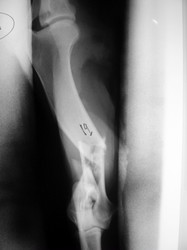

PRÁCTICAS CURSO DE FIJACIÓN EXTERNA PERFECCIONAMIENTO.

Húmero.